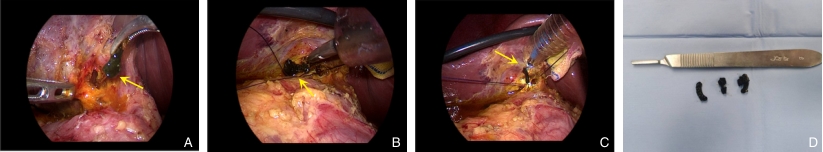

图1 患者术前影像学检查均提示胆总管扩张及其内充盈缺损(箭头所示) A:外院腹部超声图像;B:本院腹部超声图像;C:本院腹部CT平扫图像;D:本院MRCP图像Fig.1 Preoperative imaging showing dilation of the common bile duct and intraluminal filling defects (arrows) A: Abdominal ultrasound from an external hospital; B: Abdominal ultrasound from our hospital; C: Plain abdominal CT scan; D: MRCP from our hospital